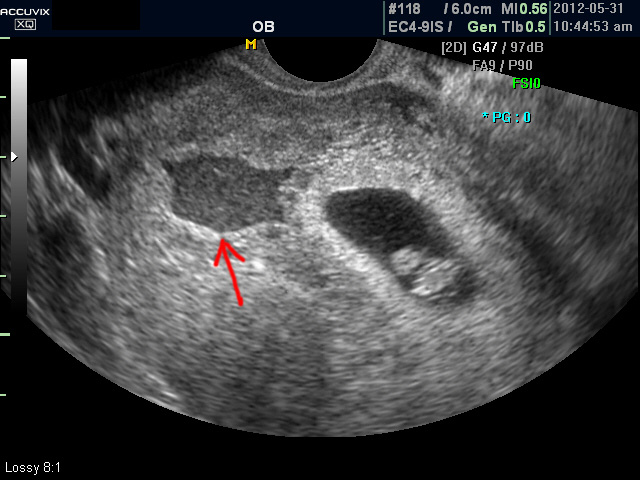

유산의  진단은 임신 증상의 소멸이나 질출혈로도 어느 정도 짐작이 가능한 경우가 있지만 최종적인 판단은 혈액 검사나 초음파 검사를 통하여 하게 되며 대개의 경우 초음파 검사로 확진을 하게 됩니다.

초음파 검사에서는 정상 임신으로 진단된 후 아기집 (태낭. G-Sac)이 보이지 않거나 평균 임신 주수에 비하여 아기집이 상당히 작을 때, 그리고 임신 8주 이후에 태아 심박동이 없는 경우에 유산일 가능성이 높다고 판단합니다.

아래는 유산과 관련된 초음파 사진으로 위 사진은 유산기가 있다고 하는 경우 (의학적으로는 절박유산)의 사진이고 아래의 사진은 고사 난자라고 하여 태아가 정상적으로 형성되지 못한 유산의 사례입니다.